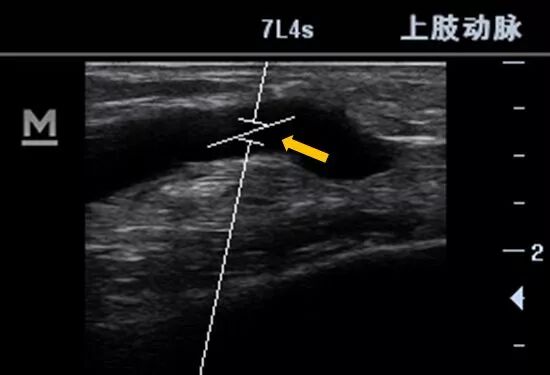

下图中,血管斜角较大,θ角为46°

什么是超声容积探头血流量测定 |取样容积和角度θ_https://www.jmylbn.com_新闻资讯_第7张

大多数肱动脉从肘部到桡尺分叉这一段有一个自然的斜角,可以利用这个天然角度。